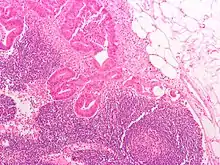

.jpg.webp)

Lymph nodes are kidney or oval shaped and range in size from 2 mm to 25 mm on their long axis, with an average of 15 mm.[2]

Each lymph node is surrounded by a fibrous capsule, which extends inside a lymph node to form trabeculae.[3] The substance of a lymph node is divided into the outer cortex and the inner medulla.[3] These are rich with cells.[4] The hilum is an indent on the concave surface of the lymph node where lymphatic vessels leave and blood vessels enter and leave.[4]

Lymph enters the convex side of a lymph node through multiple afferent lymphatic vessels and from there flows into a series of sinuses.[3] After entering the lymph node from afferent lymphatic vessels, lymph flows into a space underneath the capsule called the subcapsular sinus, then into cortical sinuses.[3] After passing through the cortex, lymph then collects in medullary sinuses.[3] All of these sinuses drain into the efferent lymph vessels to exit the node at the hilum on the concave side.[3]

Subdivisions

A lymph node is divided into compartments called nodules (or lobules), each consisting of a region of cortex with combined follicle B cells, a paracortex of T cells, and a part of the nodule in the medulla.[15] The substance of a lymph node is divided into the outer cortex and the inner medulla.[3] The cortex of a lymph node is the outer portion of the node, underneath the capsule and the subcapsular sinus.[15] It has an outer part and a deeper part known as the paracortex.[15] The outer cortex consists of groups of mainly inactivated B cells called follicles.[4] When activated, these may develop into what is called a germinal centre.[4] The deeper paracortex mainly consists of the T cells.[4] Here the T-cells mainly interact with dendritic cells, and the reticular network is dense.[16]

The medulla contains large blood vessels, sinuses and medullary cords that contain antibody-secreting plasma cells. There are fewer cells in the medulla.[4]

The medullary cords are cords of lymphatic tissue, and include plasma cells, macrophages, and B cells.